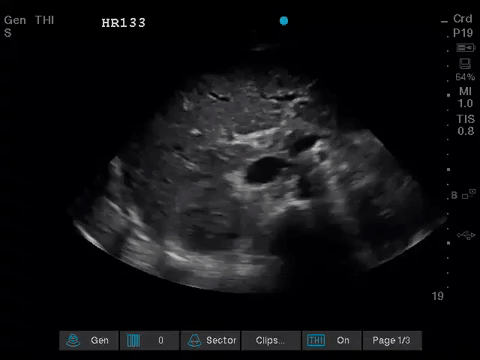

Before giving their clinical interpretation of the LUS findings, the POCUS team also scanned the heart and vasculature to obtain a more complete picture.

A comprehensive echocardiogram confirmed the POCUS findings. Her depressed LVEF was thought to be due to either septic cardiomyopathy or chemotherapy toxicity.

1. When scanning the lungs, a comprehensive, bilateral lung scan is far superior to a single clip; as this will offer more information and permit an interpretation based on the overall pattern of findings. Had this patient only had the R1 area scanned, for example, we may have reached the erroneous conclusion that her hypoxemia was likely due to pulmonary edema.

2. When scanning critically ill patients, it is almost always indicated to scan the heart, lungs, and vasculature together (as opposed to scanning a single system). You never know what you might find!